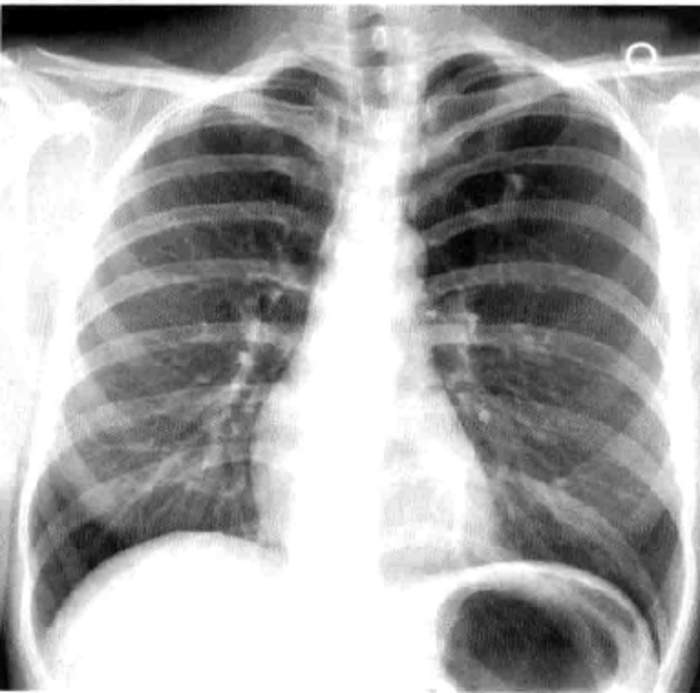

二、我可以用胸片而不是低剂量CT扫描进行筛查吗?

目前肺癌筛查的方法是低剂量的薄层CT平扫,而不是胸片。想象一下大海捞针的难度,就类似于在胸片中找一个很小的肺结节。而CT可以整个肺部分成很多细小的部分,自然更容易找到。

胸片(看整体)